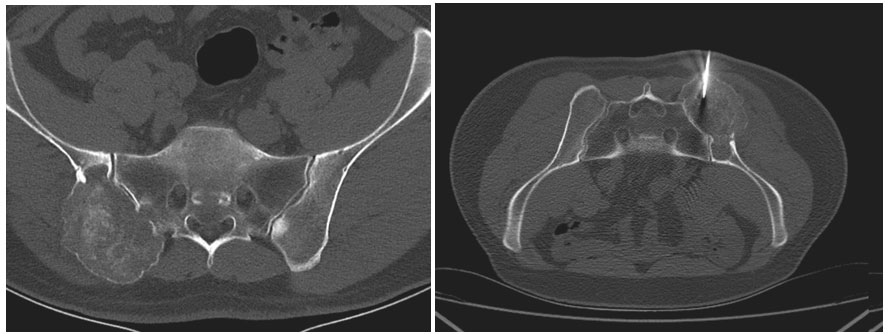

Ameliyat Öncesi: Tomografide sağ iliak kanat ve sakrum yerleşimli kemikte harabiyete neden olan tümör dokusu ve biyopsi iğnesi görülmekte